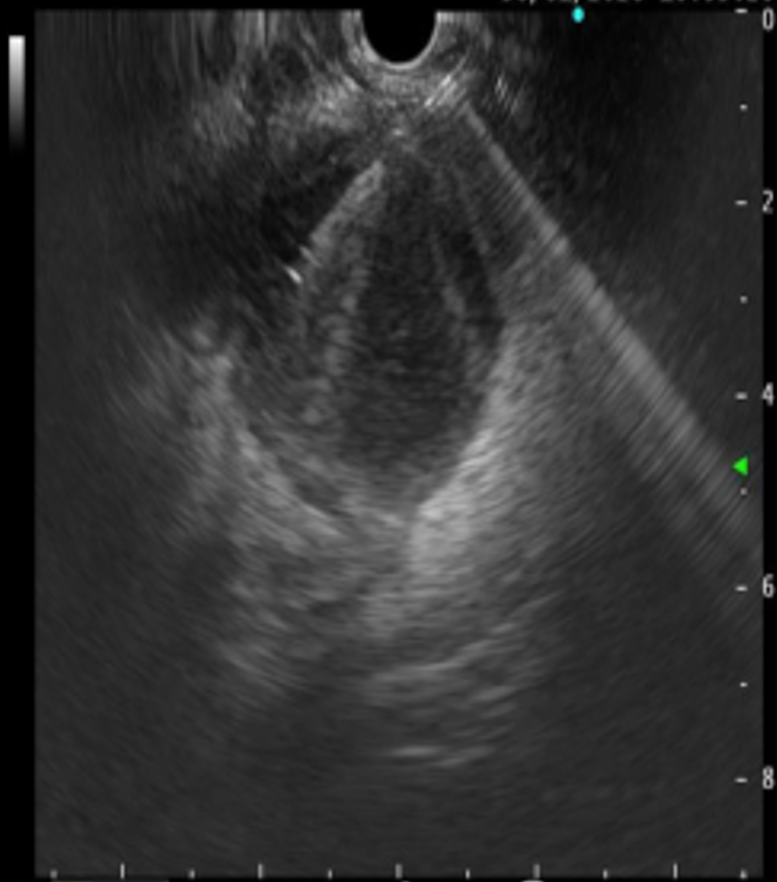

超声内镜引导下脓肿穿刺

经过充分的术前准备,消化内科刘华副主任医师在毛涛主任的指导下,和麻醉科、内镜室医护团队的密切配合下,凭借精湛的内镜技术,仅用时20分钟,便通过实时超声精准锁定病灶位置,巧妙避开血管、神经等重要解剖结构,合理规划穿刺路径并成功置入支架。手术全程经人体自然腔道操作,无体表切口,且未对直肠功能造成损伤。